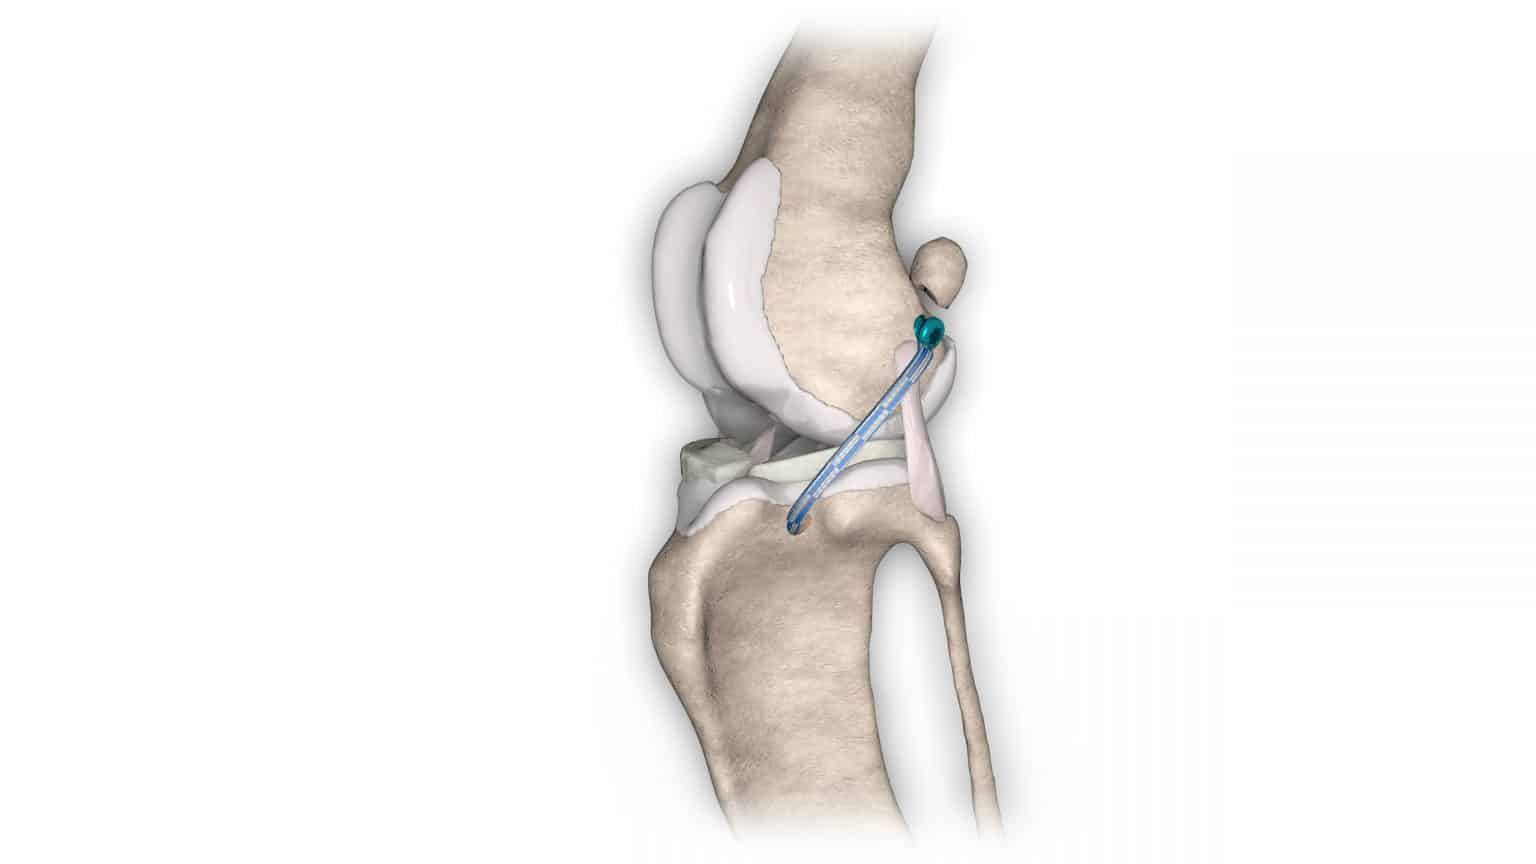

V případě ruptury kraniálního zkříženého vazu umožňuje ExtraTape® extraartikulární rekonstrukci co nejblíže izometrii původního vazu, čímž rychle a trvale stabilizuje koleno bez uzlů a zvlnění, což je slabina tradičnějších technik extraartikulární stabilizace. Ty jsou zde nahrazeny pevným ukotvením kosti pomocí interferenčního šroubu.

Řešení, které respektuje původní anatomii, obnovuje funkci postiženého vazu a je dostupné v rámci otevřené nebo artroskopické chirurgie.